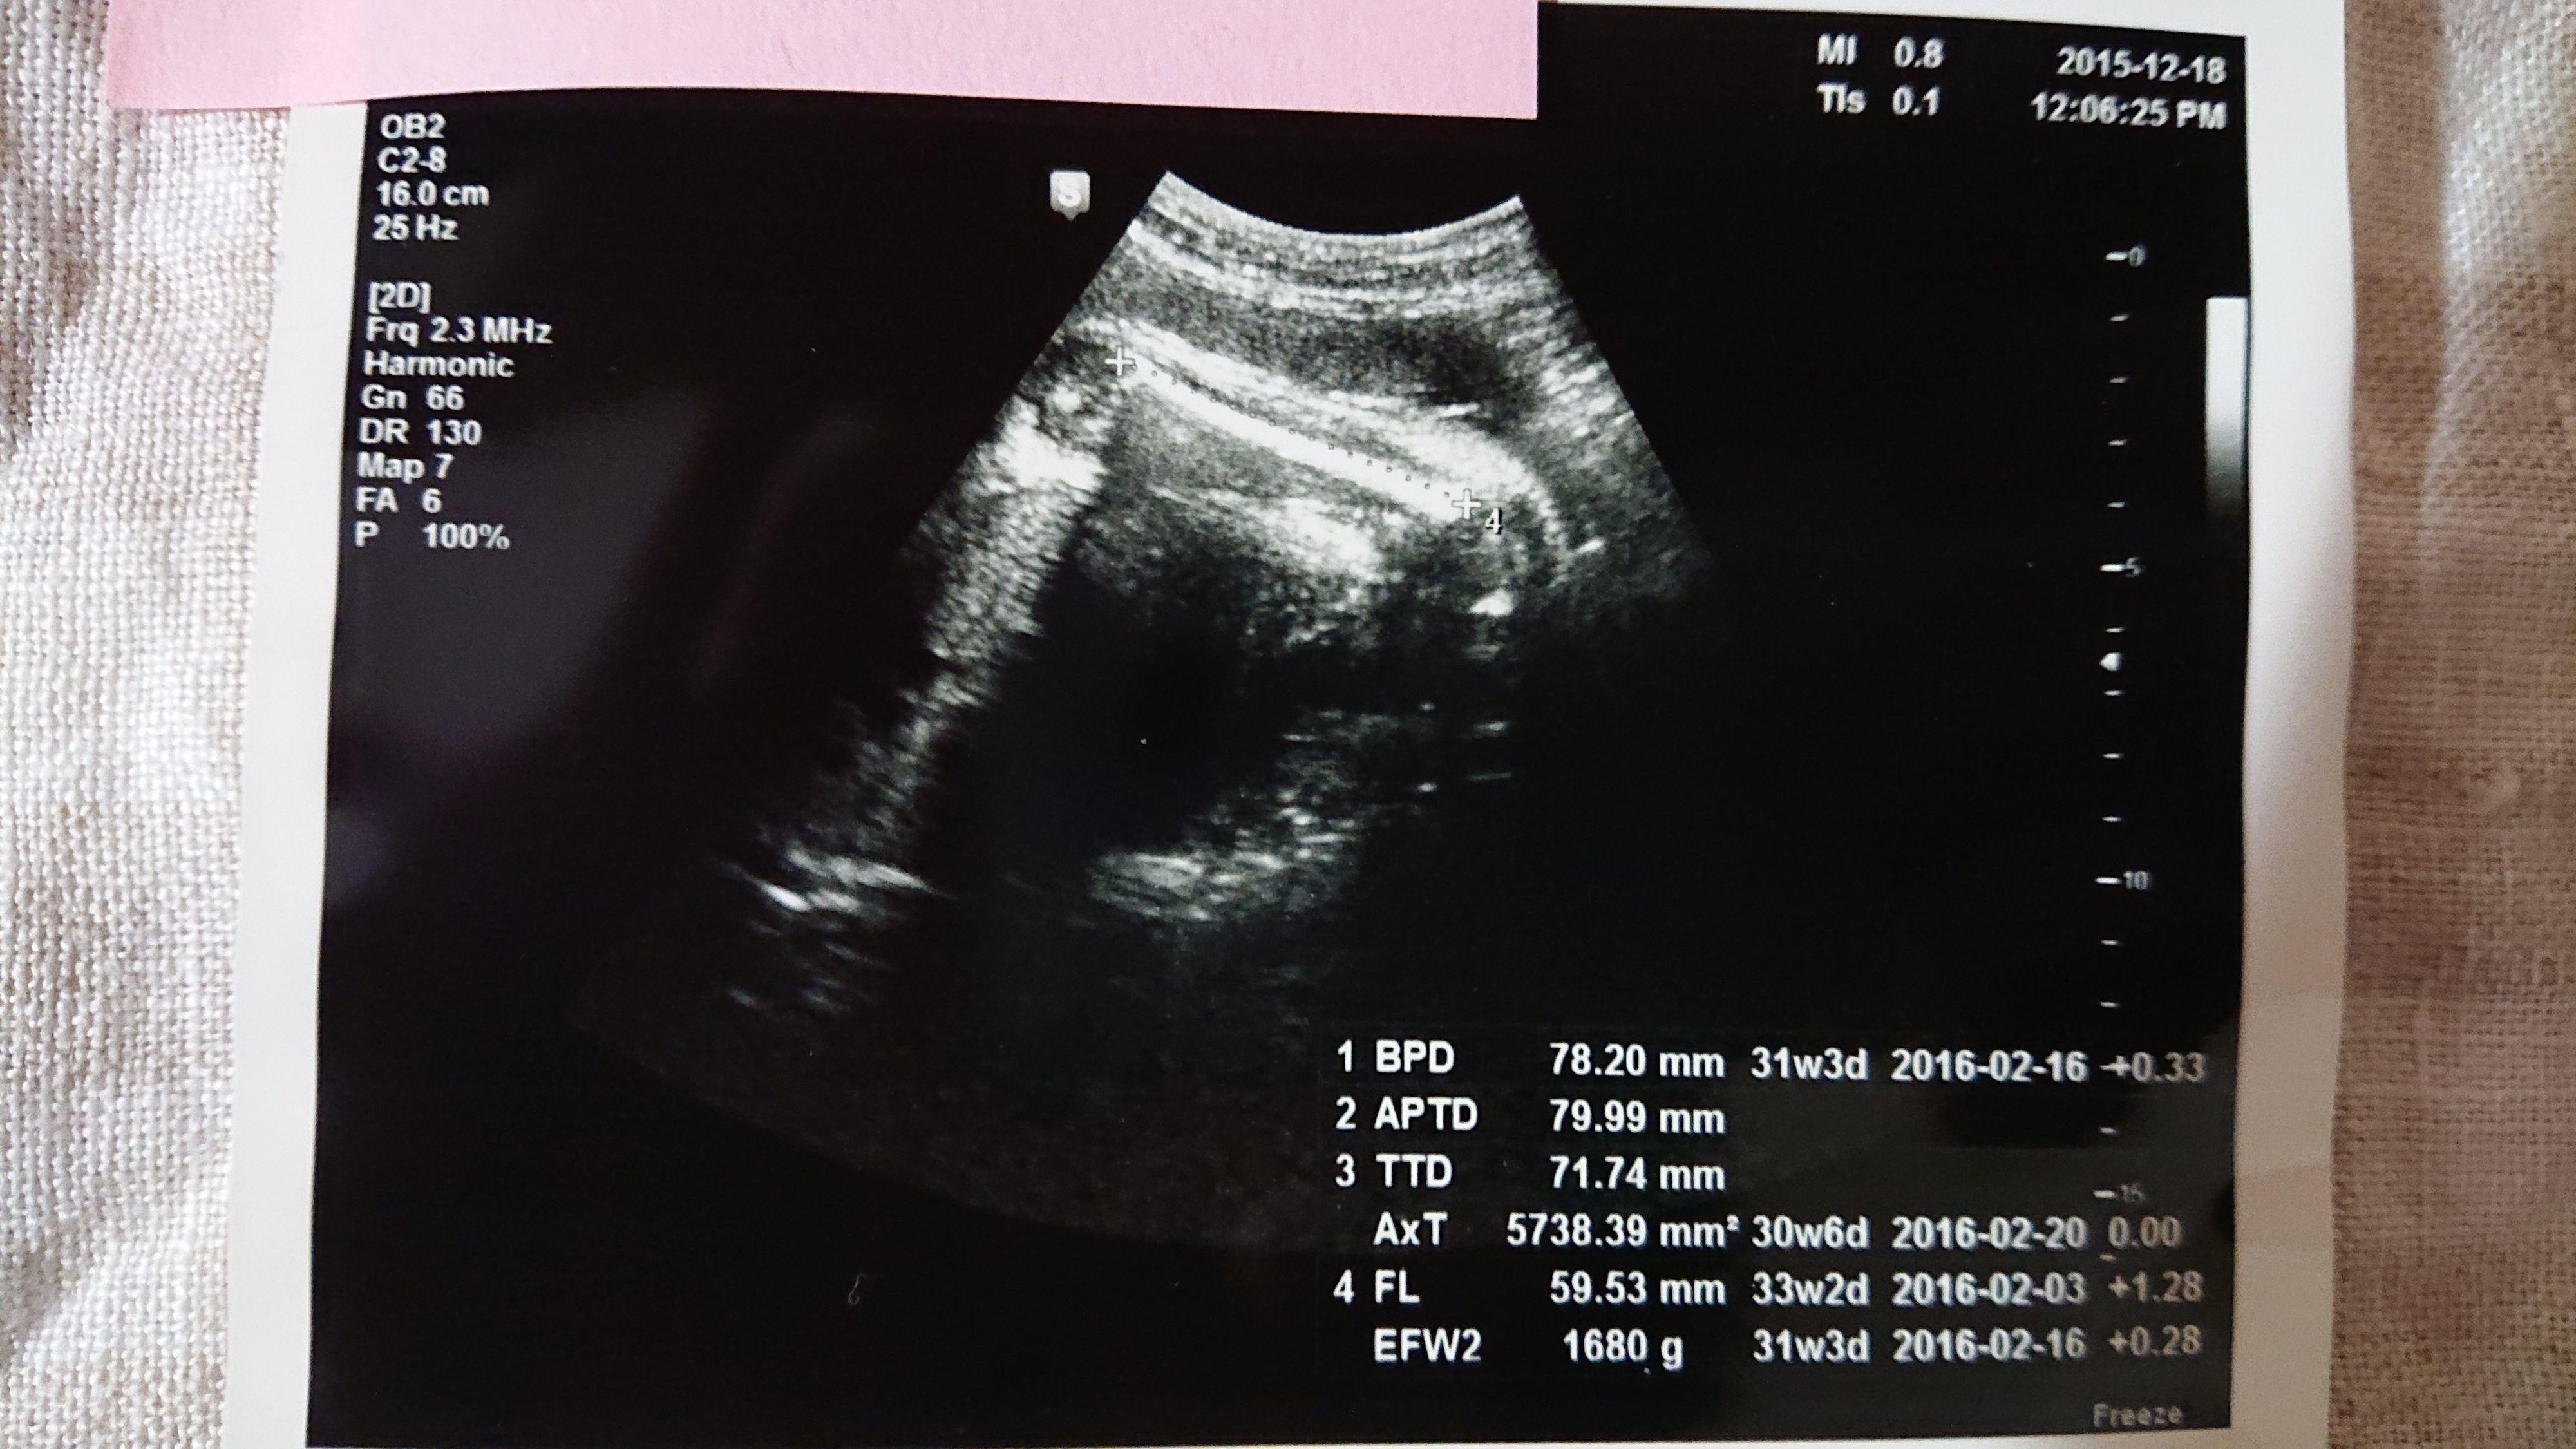

《妊娠30週目のエコー写真》

この写真を撮る2週間程前に切迫早産で入院してしまったのですが、入院してから初めて撮った30週目のエコー写真です。妊娠後期になってくると、赤ちゃんが大きくなりすぎて、ほんの一部しかエコー写真に写らなくなってきました。「赤ちゃんの顔が見たい」と思っても、この日は赤ちゃんの向きが合わずに見ることができませんでした。「赤ちゃんの向きによって、赤ちゃんの顔を見られずに終わってしまう時もある」と、医師に言われて、何だか残念に思ったものです。